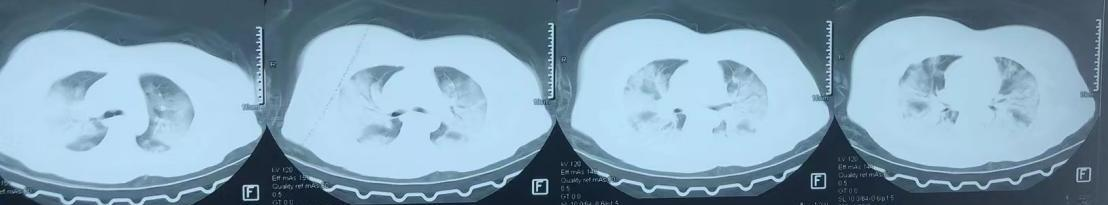

据悉,34岁的患者史某于1月中旬出现发热、咳嗽,初期考虑为“普通感冒”,在当地医院治疗一周后病情加重,肺部CT提示双肺病变,1月21日转入湘雅三医院急诊,因“呼吸衰竭”行气管插管呼吸机辅助呼吸后转入内科ICU,呼吸与危重症医学科刘纯主任医师团队立即开展救治。

重症肺炎患者,病原体不明,刘纯凭借多年的呼吸危重症抢救经验,积极迅速地收集临床资料、完善相关检查,很快锁定病原体——乙型流感病毒。但由于抗病毒时机太晚,治疗效果欠佳,紧接着并发耐药细菌感染,肺部情况反复恶化,多次生死一线。在多学科MDT合作下,团队为患者制定了周密严谨的个性化治疗方案。